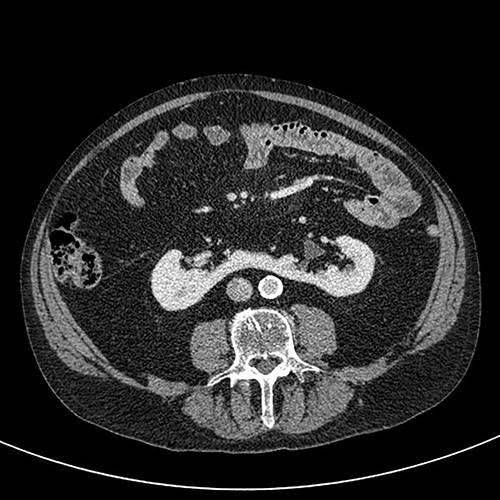

A 76-year-old gentleman with a background of benign prostatic hyperplasia, hiatus hernia, and anxiety was referred to the rapid access haematuria service following an episode of painless visible haematuria. Flexible cystoscopy did not reveal any concerning bladder lesions. CT Urogram demonstrated a horseshoe kidney with a filling defect in the left upper pole moiety suspicious for an urothelial carcinoma (Figs 1 and 2). The patient was subsequently referred to the urology services in a tertiary centre. Flexible ureterorenoscopy was performed, with findings of a likely urothelial carcinoma corresponding to the suspicious area on imaging. Biopsy of this lesion revealed a low grade urothelial cancer.

Coronal CT (urographic phase) demonstrating filling defect left upper pole.